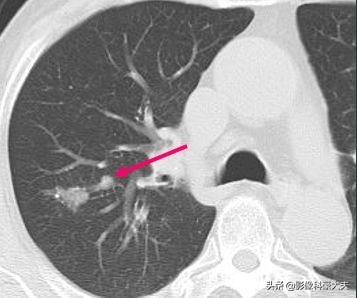

这个病人没有症状,结节比较光滑,会不会是结核球?我们不急于定论,先利用设备的强大后处理功能把图像放大后,观察到两个细节:

肺门侧有一个小结节,首先考虑淋巴结(局部转移),同时结节的远侧带一点光滑的小尾巴,这提示早期转移,淋巴浸润的可能,最符合小细胞肺癌的特点。进一步给病人做了增强扫描,显示这个小结节呈轻度强化(小细胞肺癌大多乏血供,多呈轻度强化),这就不应该直接手术了,需要先穿刺明确病理,因为如果是小细胞肺癌,转移早,进展快,手术不能获益(只有大约5%的局限期小细胞肺癌可以手术)。